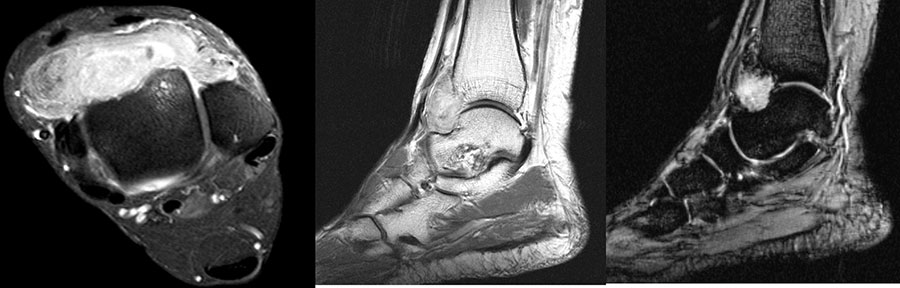

MR-tomographische Darstellung eines unspezifischen weichteiligen Raumforderug im Bereich des dorso-lateralen Rückfußes. Die offene Probebiopsie ergab schließlich die Diagnose eines hochmalignen Synovialsarkoms.

Abbildung 34